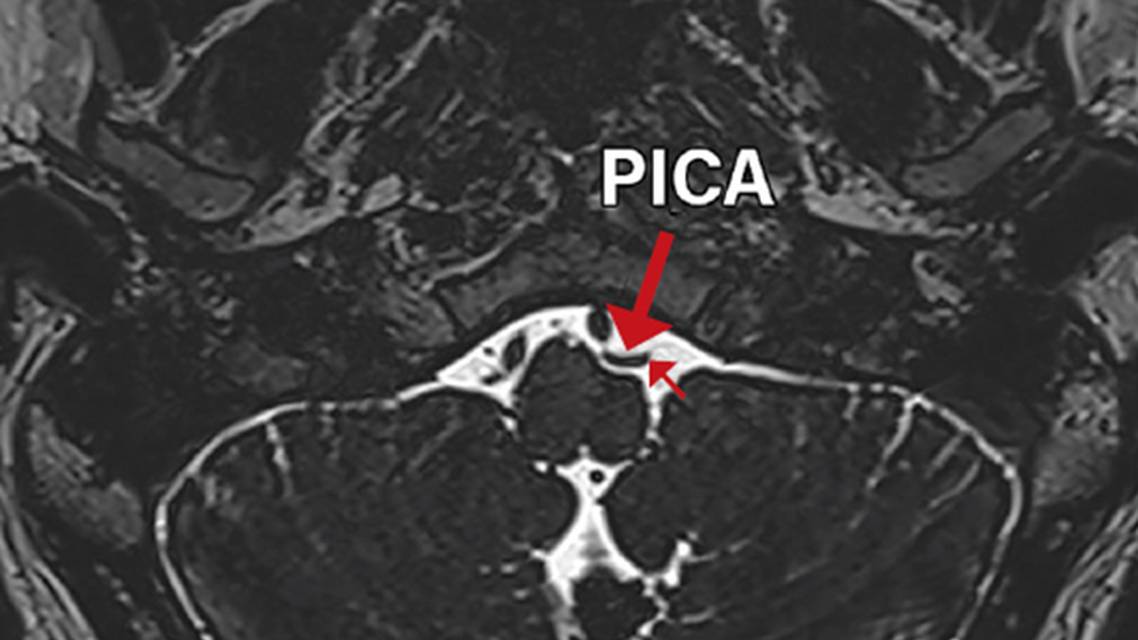

A repeat MRI taken 13 months later showed marked deviation and deformity of the left hypoglossal nerve root and neurovascular contact with a redundant left posterior inferior cerebellar artery (PICA) in the cisternal segment (Figures 1 and 2).

The patient in Case 3 was anxious about ALS to the point that his primary care physician prescribed benzodiazepines. The success of repeated imaging in detecting a likely cause of his symptoms demonstrates the utility of imaging for following up on patients with idiopathic IHNP. To our knowledge, this case is the first in which an etiology was identified after a provisional idiopathic diagnosis for such a long period of time. If a vascular etiology is confirmed, this patient may benefit from microvascular decompression of the hypoglossal nerve, which has reportedly been successfully performed.7

The patients in the cases presented here all received the comprehensive diagnostic workup that has been proposed for evaluating hypoglossal nerve palsy (Table 2),5,14 which effectively excluded the above conditions. For the patient in Case 3, imaging findings specifically denoted a lack of abnormalities in the cisternal segment of the affected nerve. It is possible that a vascular disease process undetectable at the time of initial imaging progressed to become detectable on imaging 13 months later.